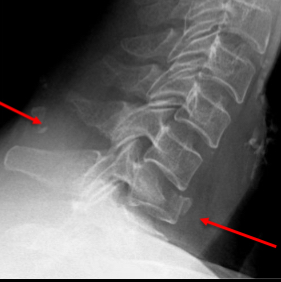

what is a hangman’s fracture?

Historically due to hanging but also seen

in RTC’s where the face strikes the

windscreen forcing the neck into

hyperextension.

• Hyperextension and distraction results

in bilateral fractures through the pedicles

of the axis (C2), with anterior dislocation

of the body and subsequent tearing of

the spinal cord

What is a flexion teardrop fracture?

Highly unstable.

• The posterior and anterior longitudinal

ligaments are disrupted.

• Posterior displacement of the vertebra the

spinal canal.

• Disruption of the posterior portion of the

vertebra above.

• Stress applied to the anterior longitudinal

ligament causes it to avulse from the

vertebral body along with a “teardrop”

shaped bony fragment.

• Most common at C5/6 and C6/7